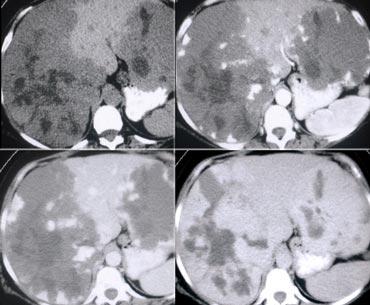

NECT, arterial and portal venous phase in a patient with Hepatitis C with two lesions in the liver (arrows).

Trong thì động mạch, chúng ta thấy hai tổn thương tăng sinh mạch.

Các hình ảnh phía trên cho thấy một tổn thương đồng tỷ trọng với gan trên CCLVT không tiêm thuốc.

Trong thì động mạch có sự ngấm thuốc, nhưng không đậm bằng tỷ trọng máu trong lòng mạch.

Trong thì tĩnh mạch cửa, tổn thương lại đồng tỷ trọng với nhu mô gan xung quanh và không thể nhìn thấy.

Nếu chỉ có thì tĩnh mạch cửa, chắc chắn bạn sẽ bỏ sót tổn thương này.

Các hình ảnh phía dưới cho thấy một tổn thương có thể nhìn thấy trên tất cả các hình ảnh.

Bạn thấy nó trên CCLVT không tiêm thuốc và có thể nhận xét rằng nó giảm tỷ trọng so với gan.

Tuy nhiên, nếu nhìn vào tỷ trọng máu trong lòng mạch, bạn sẽ nhận thấy rằng ở tất cả các thì, tổn thương có tỷ trọng tương đương với máu trong lòng mạch.

Vậy chúng ta có một ung thư biểu mô tế bào gan ở thùy phải trên các hình ảnh phía trên và một u máu ở thùy trái trên các hình ảnh phía dưới.

Điều quan trọng là phải xem xét tất cả các thì chụp.